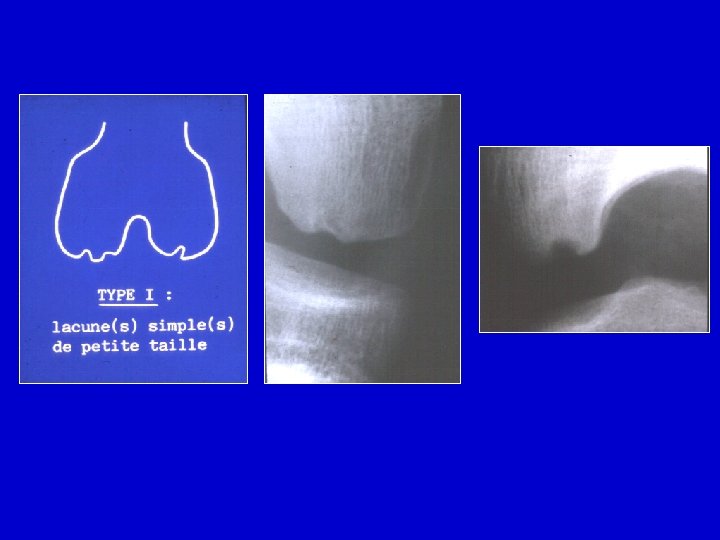

Radiografie • All’inizio la zona di necrosi appare condensata Le cartilagine é intatta • Più tardi il frammento si può separare dall’osso vicino • Le cartilagine può restare intatta • Il frammento può staccarsi e migrare nell’articolazione

Radiografie semplici

I : Cartilagine II : osso necrotico separato III: tessuto fibroso IV : zona necrotica V : Osso normale

Determinare la largezza e la profondità della zona necrotica